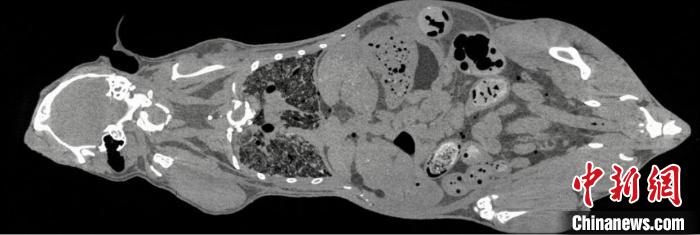

鼠全身成像

鼠钆剂造影成像